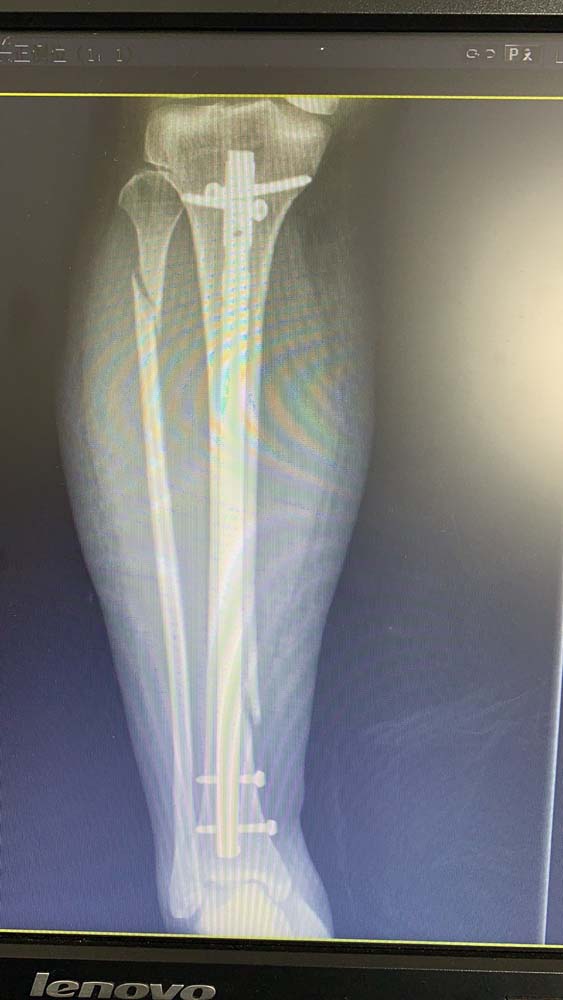

到达医院急诊后,化伟立即为张女士进行了X光片检查。果然,张女士右小腿下段胫骨骨折,右小腿上段腓骨骨折。吴飞华又披上白衣“战甲”,亲自操刀,为张女士进行急诊手术治疗,并收在医院8D病区住院治疗。

住院期间,8D病区医护团队为行动不便的张女士进行了悉心治疗和护理。好在张女士年纪轻,身体素质好,吴飞华为她进行了胫骨骨折闭合复位髓内针内固定术后,她的右腿经过一周时间的恢复和训练,已经达到了出院的标准。出院当天,张女士虽然坐在轮椅上,但还是连连向8D骨科的医生和护士们表示感谢。她说:“我这一跤虽然摔得重点,但是遇到了我的贵人——吴飞华医生和陶玲云护士,更遇到了一群好人——垂杨柳医院骨科的医生们和护士们。你们手术做得好,护理也做得好。有你们在,我这个本命年的坎啊,平安度过啦!”